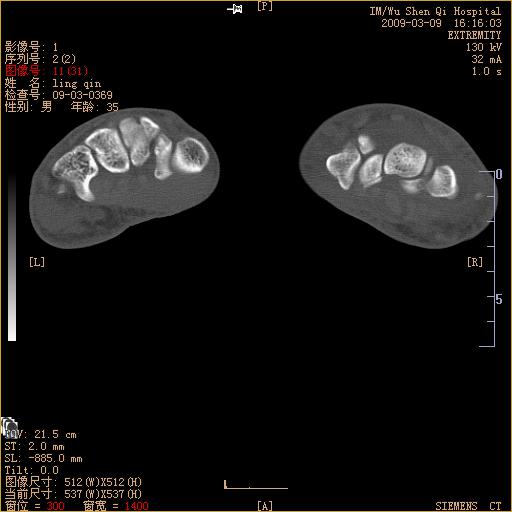

标题: CT18570:右手外伤10余天 [打印本页]

标题: CT18570:右手外伤10余天

腕部有骨折、脱位,骨科面对ct片如何采取措施?三维一下。

左侧舟骨及桡骨茎突骨折,第一掌骨基底部好像也有骨折,建议上传平片